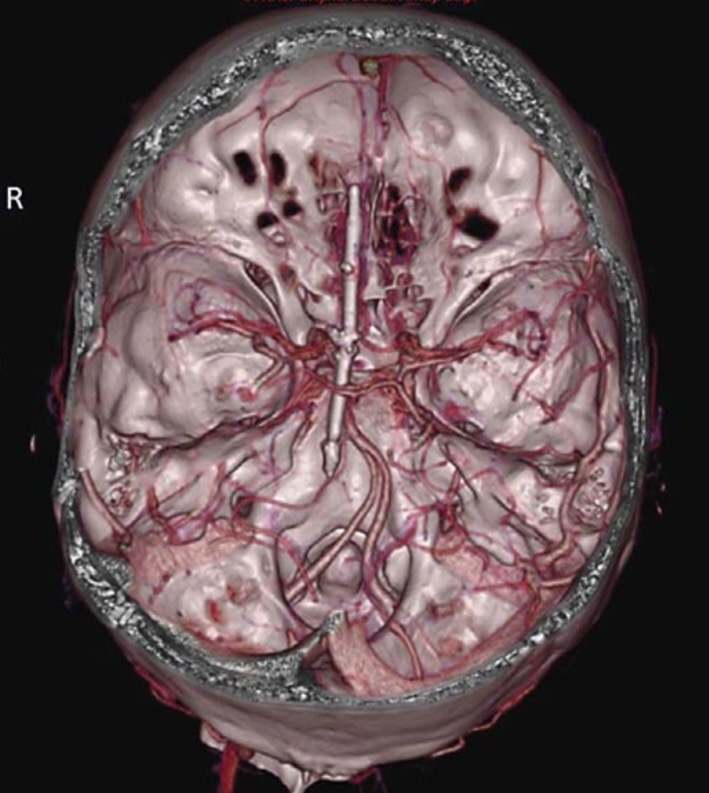

Figure 3. Осевой вид трехмерной компьютерной томографии, показывающий связь швейной иглы с сосудистыми структурами.